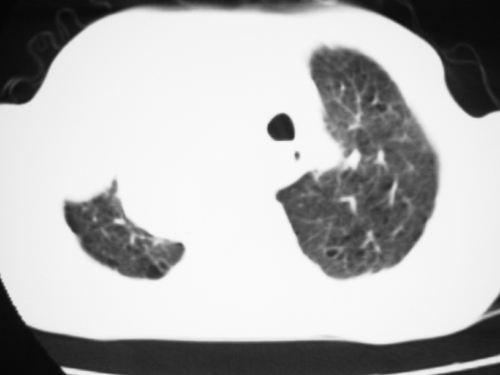

以下是引用yangyudong333在2008-4-29 5:46:00的发言:[br]1左上叶结节呈分叶状,边缘毛刺,考虑肺癌并纵隔淋巴结转移可能性大,结核待排,[br] [br]2右侧多发包裹性胸腔积液

以下是引用zsl6918在2008-4-29 9:15:00的发言:[br]右侧包裹性积液穿刺术后改变,肺内多发结节不除外转移可能。建议查胸水,问病史。